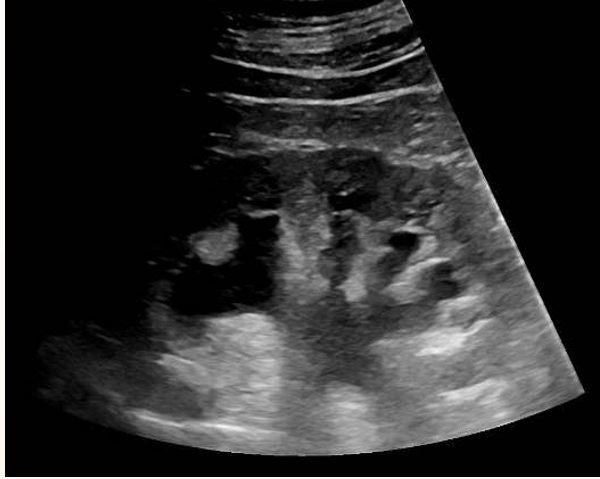

Hombre de 69 años. Antecedentes personales: diabetes mellitus tipo 2, hipertensión arterial, hipercolesterolemia.Acude a Urgencias por astenia progresiva de un mes de evolución y recorte de diuresis. Exploración: palidez mucocutánea. Normotenso y eupneico. Auscultación cardiorespiratoria normal. Abdomen globuloso, blando, no doloroso. Analítica: Hb 9 (previa 11 dos meses antes), urea 160, creatinina 10,9 (previa 1,7), proteína C reactiva 120. Resto anodino (no leucocitosis ni alteraciones iónicas, urianálisis negativo). EFNa: 14% (posrenal). Ecografía renal, que evidencia hidronefrosis bilateral grado III, sin causa obstructiva aparente. Dada la evolución tórpida pese a sueroterapia y diuréticos, se realiza TAC abdominal para continuar estudio de la causa obstructiva: aneurisma de aorta abdominal infrarrenal, con rotura contenida por hematoma y compresión extrínseca de ambos uréteres.

Respecto a la Ecografía, es esencial una sistemática de exploración minuciosa para mayor rentabilidad diagnóstica. La generalización del uso de la ecografía Atención Primaria y en Urgencias supone un diagnóstico más rápido y preciso, y por tanto una mejor atención al paciente.